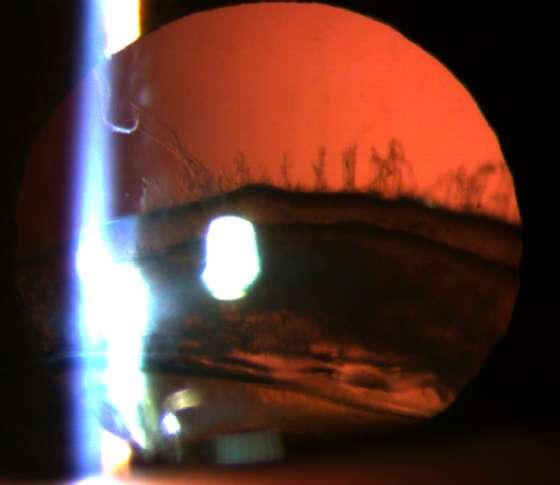

ü Gonioscopía (Imagen C): Ángulo abierto en en 270º, trabéculo con pigmento, SAP inferior

ü Fondo de ojo (Imagen D): Papila pálida con excavación 0.9. macula sana

ü El Sd. UGH es una complicación que puede aparecer en el post operatorio (precoz o tardío) luego de la implantación de un lente intraocular.

ü Se define clásicamente por la triada que su nombre comprende, aunque pueden aparecer formas incompletas.

ü La incidenccia se ha visto aumentada debido al incremento de la cirugía de cristalino, ya sea por catarata o con finalidad refractiva.

ü La patogenia se debe a la presión ejercida por los hápticos del lente intraocular (LIO) sobre el tejido uveal y puede presentarse en paciente con lentes en cámara anterior, sulcus o saco.

ü Sospechar en paciente pseudofáquico con episodios recurrentes de uveitis no filiada C D